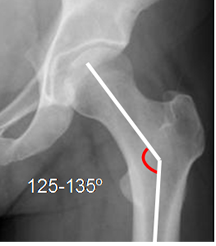

Mediciones importantes a la hora de valorar la patología de la cadera.

Fig 16. Angulo cervicodiafisiario normal.

Fig 18. Angulo de cubrimiento lateral normal.

Rx AP de cadera.